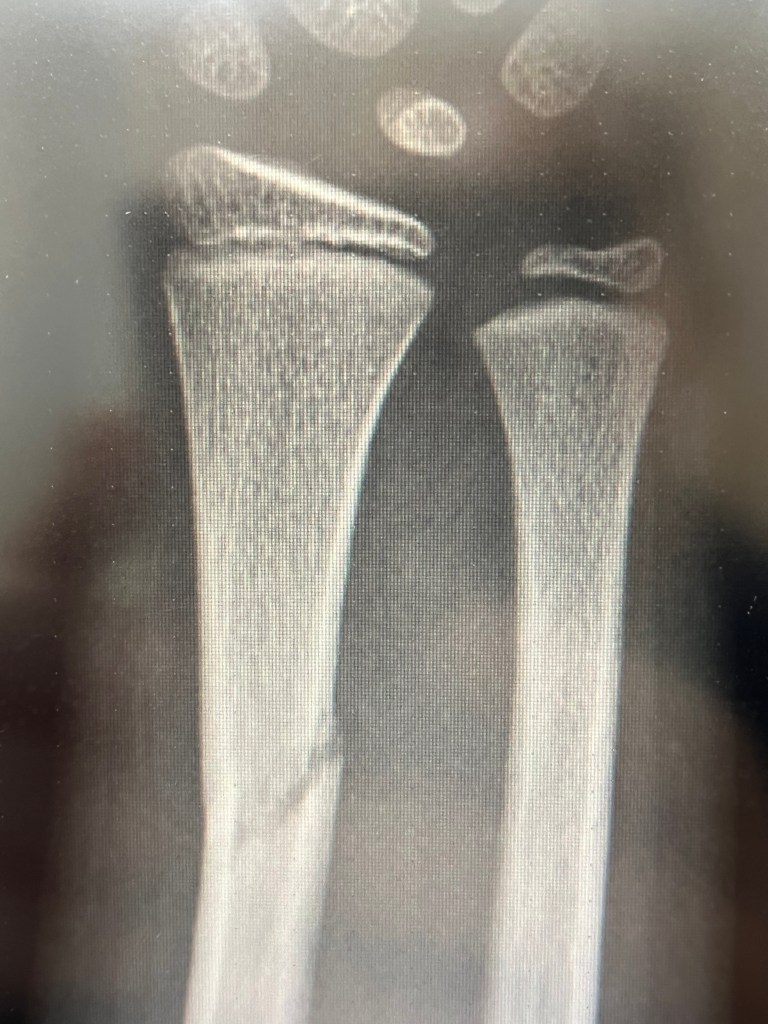

K’s Broken Arm Published on September 18, 2025March 26, 2026 by cak5157 Share this: Share on X (Opens in new window) X Share on Facebook (Opens in new window) Facebook Like Loading... Related